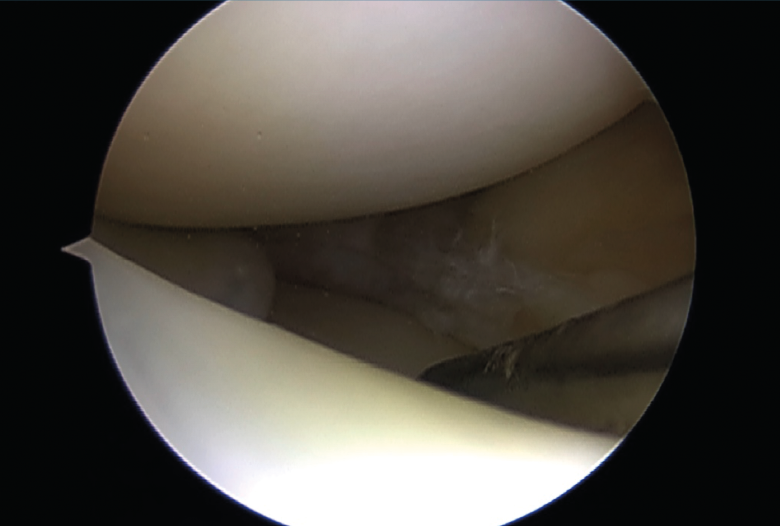

Figura 1. Rotura meniscal en asa de cubo.

El tratamiento artroscópico de las lesiones meniscales está indicado en aquellas lesiones que produzcan bloqueo articular, pacientes sintomáticos que no mejoren con tratamiento conservador o aquellos en quienes se vea afectado su nivel deportivo o laboral (Figuras 1 y 2).